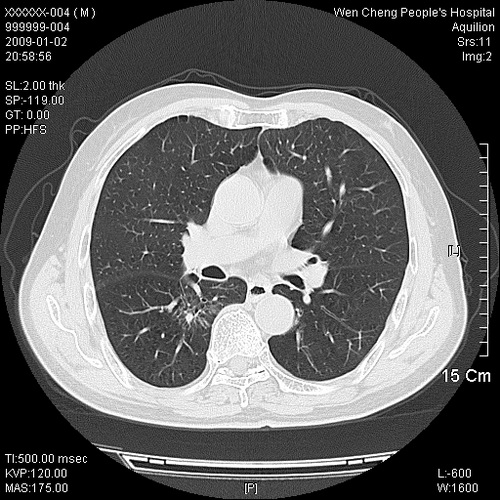

男性,73岁,有慢支病史,肿瘤系列标志物检验正常,血沉及血常规正常

右肺下叶背段小片状 磨玻璃样模糊影,内见血管及含气支气管像,支气管管壁增厚。考虑:慢性炎症!

右肺下叶背段小片状 实性与磨玻璃样影,内见血管及含气支气管像,支气管管壁增厚,边缘见长毛刺影。考虑:慢性炎症或肿瘤!建议抗炎治疗复查,密切观察随访!

右肺下叶片团状影内见扩张的含气支气管和支气管管壁增厚,其周有磨玻璃样模糊影和长毛刺。考虑慢性炎症可能性大。

高度提示细支气管肺泡癌,建议抗炎治疗半月观察病灶变化,如无明显改变,建议立即手术治疗.

病变形态非常不好呀,临床上血常规及症状也不明显,不太支持炎性病灶,高度警惕肿瘤病变,最好做个纤支镜检查。